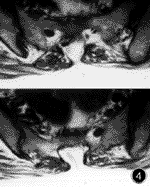

脂肪栓塞綜合徵細胞顱腦創傷:有頭部外傷史,可以表現為典型的昏迷——清醒——再昏迷病象,第二次昏迷往往逐漸發生,而且有顱腦高壓的表現;常有血壓增高,心率緩慢,呼吸減慢,臨終期才出現去大腦強直,腰椎穿刺、MRI、CT’等檢查有陽性表現。昏迷期可檢查出局部神經體徵。

發生率約86%。起始症狀包括譫妄不安、嗜睡和意識模糊,繼續發展可致昏迷。如治療及時,大部分病人可以完全恢復,但因大腦皮質的高敏感性可能留下不同程度的後遺症,輕者如個性變化、創傷後緊張綜合徵等,重者如四肢癱、癲等嚴重神經病理學障礙。合併頭部外傷的複雜骨折病人,其神經病理學表現的原因常難以確定,而受傷後至出現初期神經症狀的間隔時間有助於診斷。